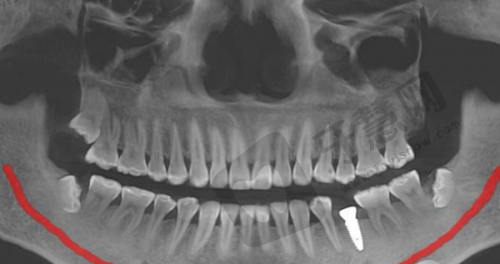

预约注意事项:在预约时,建议你提前了解一下医院的上班时间,合理安排自己的就诊时间。同时,更好准备好之前的口腔检查资料,如 X 光片等,这样医生在就诊时可以更全方面地了解你的口腔情况,为你制定更合适的治疗方案。预约成功后,记得按照预约的时间准时前往医院就诊,以免耽误治疗进度。

李先生的实例:有一位李先生,他因为意外导致牙齿缺失,并且伴有局部骨缺损的情况。在了解到泉州石狮星雅口腔局部骨缺损种植 4500 元起这个项目后,他抱着试试看的心态来到了医院。医生们首先对他的口腔进行了全方面的检查,包括拍摄X光片等,正确地评估了他的骨缺损情况。根据李先生的具体情况,医生为他推荐了韩国登腾种植体,价格比较实惠,而且性能也比较适合他的口腔状况。在种植过程中,医生采用了骨增量技术,植入了骨粉来增加骨量。整个种植过程非常顺利,李先生在麻醉的作用下没有感觉到明显的疼痛。术后,医生为李先生提供了详细的护理指导,告诉他如何正确刷牙、饮食等。李先生按照医生的指导进行护理,修复得特别快。几个月后,种植体与牙槽骨完全融合,李先生装上了牙冠,修复了正常的咀嚼功能。他对种植成效非常满意,觉得泉州石狮星雅口腔的医生技术好,服务也周到,而且价格也特别合理。